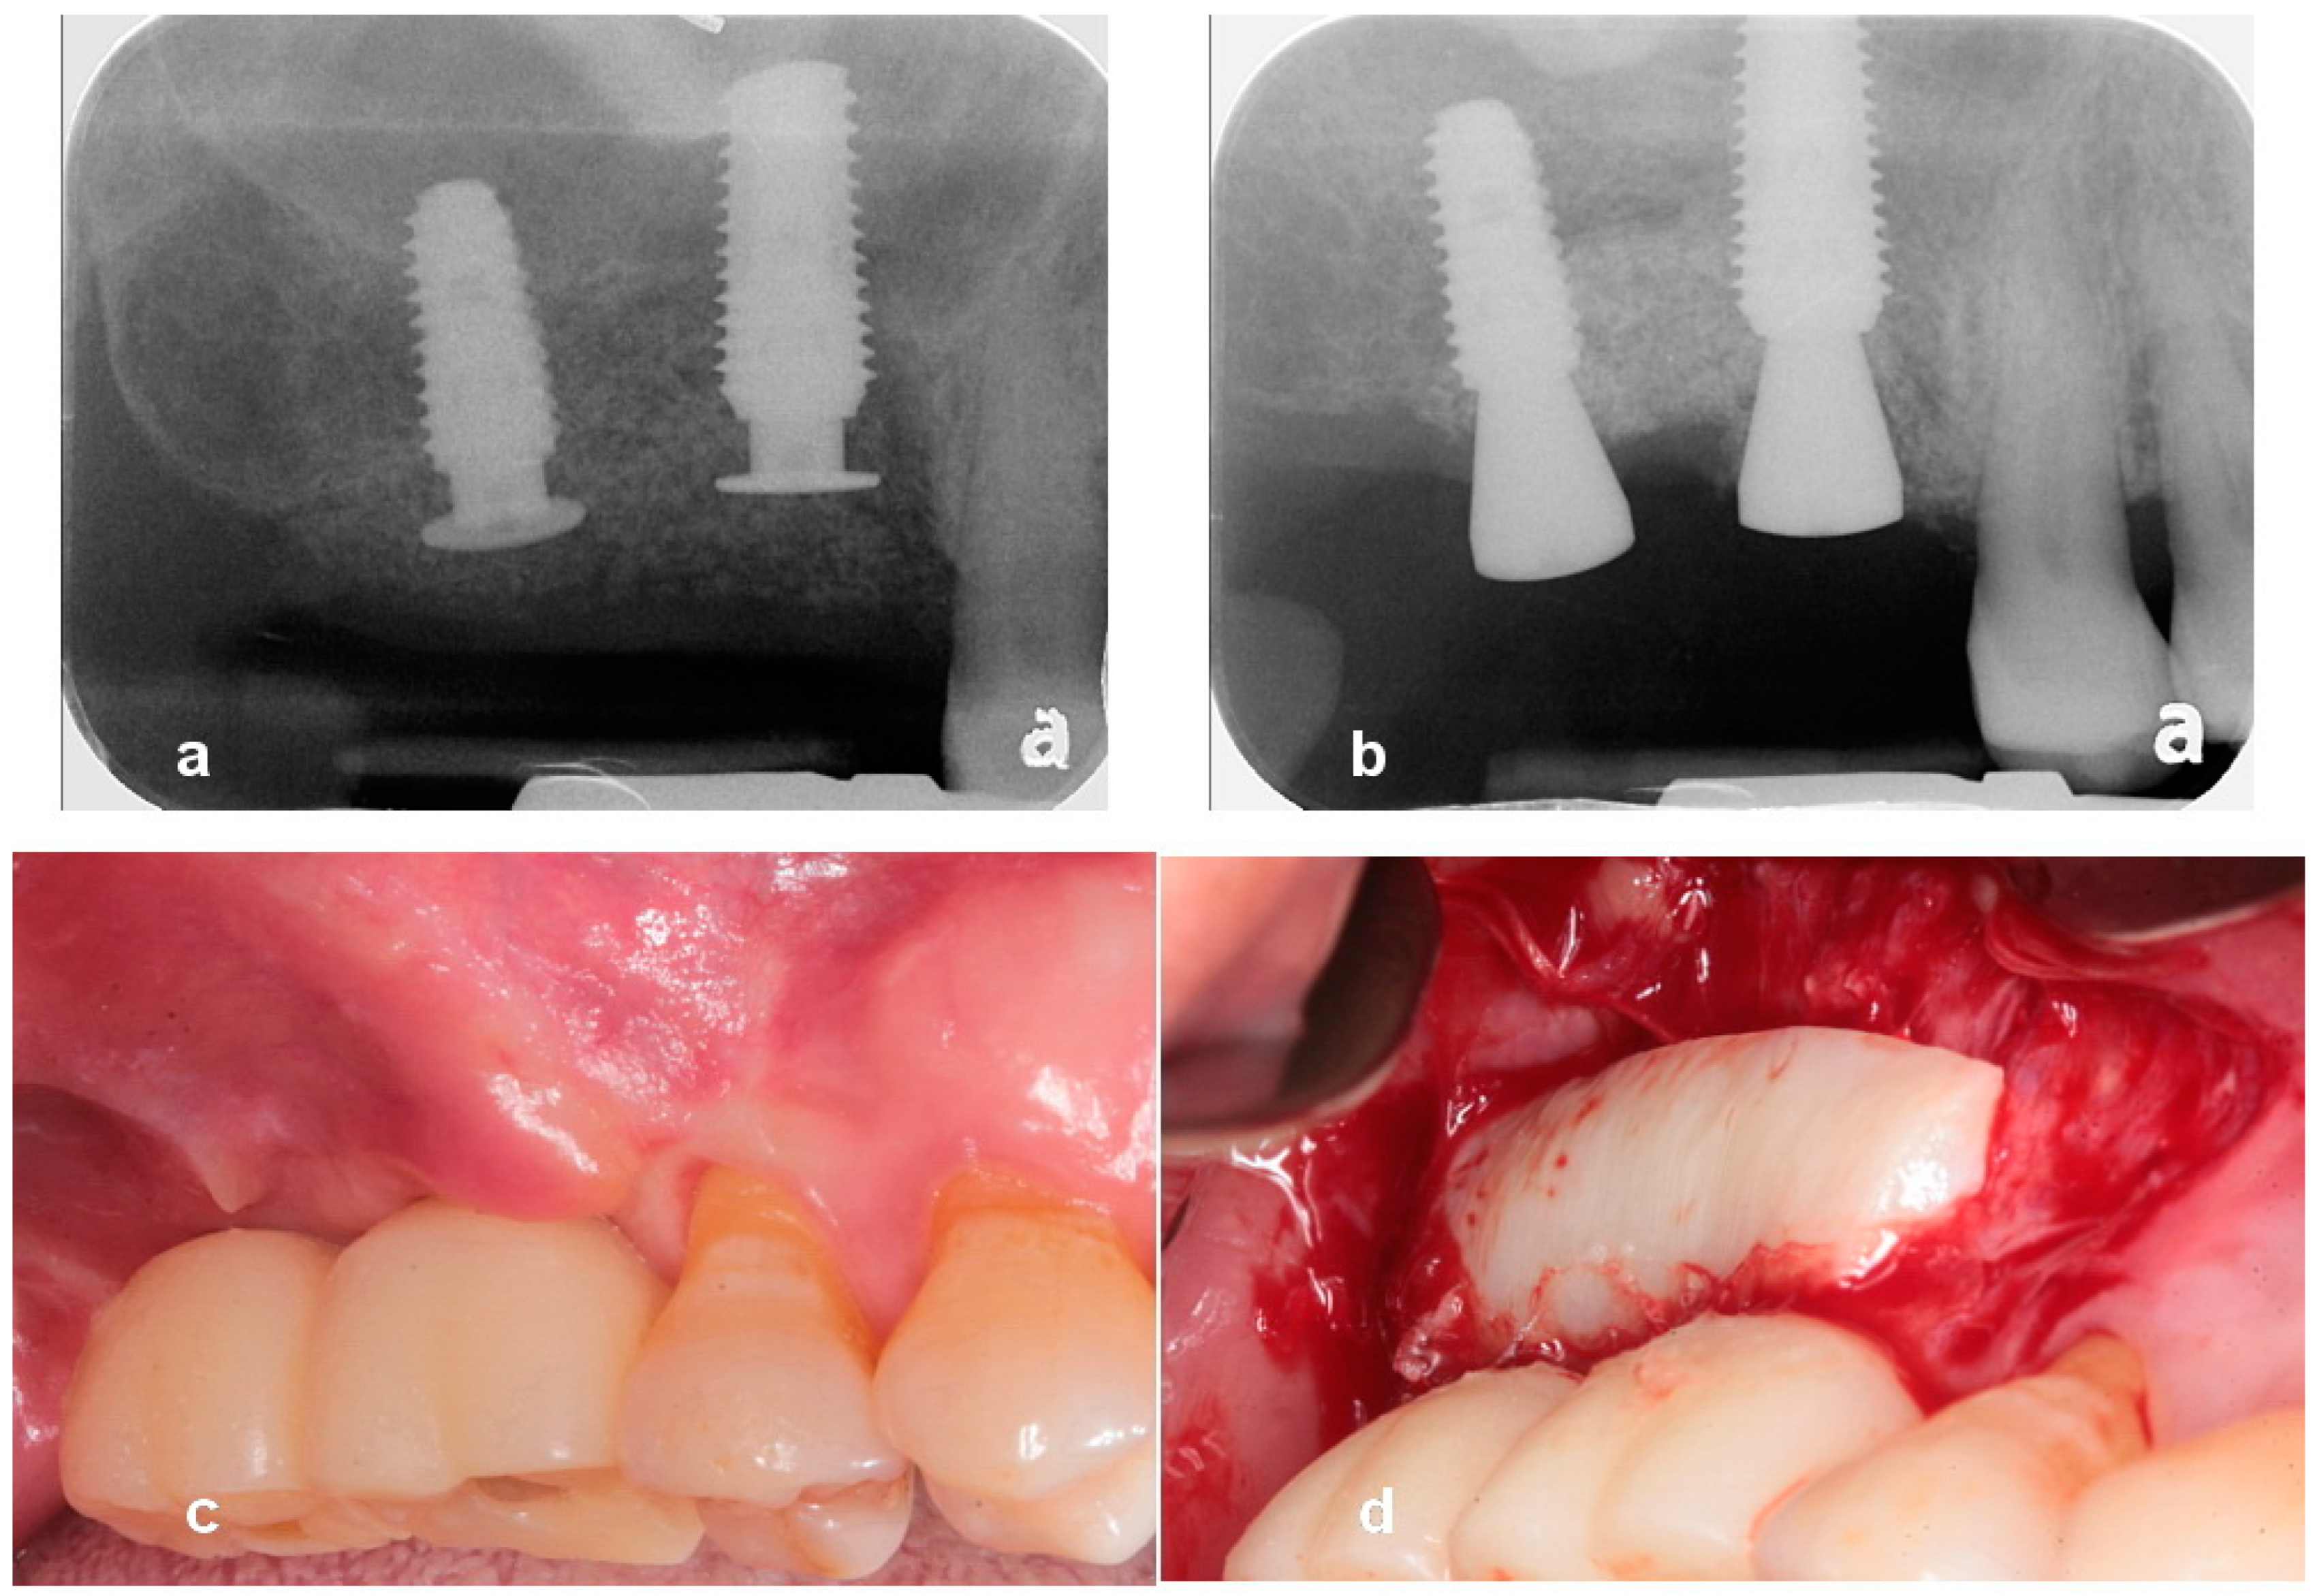

Utilization of Tenting Pole Abutments for the Reconstruction of Severely Resorbed Alveolar Bone: Technical Considerations and Case Series Reports

2. Case Presentations